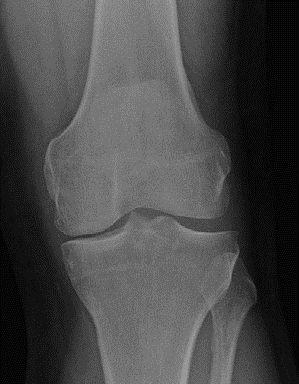

(Figure 3.4.) CANDIDATE : This is a weightbearing AP radiograph of left knee demonstrating moderate medial compartment osteoarthritis. The lateral compartment appears normal. There is a varus deformity of less than 10. I would like to take a history and examine the patient. The examination is focused mainly on localizing the tenderness, range of motion, if the varus deformity is correctable and stability of knee.

Figure 3.4

Anteroposterior (AP) radiograph knee. EXAMINER : The patient is fit and well, states that the pain is affecting his job and he would like to consider a surgical option. What would you offer him? CANDIDATE : The options of surgical management once conservative measures have failed include HTO, unicondylar knee arthroplasty or total knee replacement. Since this patient has a high-demand physical job, I would offer him HTO. EXAMINER : What are the prerequisites of HTO? CANDIDATE : A physiological age of < 60 years, fixed varus deformity < 15 or valgus deformity < 12, fixed flexion deformity of < 15, > 90 flexion. EXAMINER : Are you aware of any contraindication for HTO? CANDIDATE : The main contraindications are inflammatory arthropathy such as rheumatoid arthritis and psoriatic arthropathy, incompetent medial collateral ligament or ACL, large varus thrust with coronal subluxation of > 1 cm, severe OA of medial compartment or lateral compartment/PFJ and more than 20 of correction. Obesity is also a contraindication because valgus knee is poorly tolerated due to medial thigh contact. EXAMINER : The patient tells you that he has heard about partial knee replacement and is keen to consider the option. How do you proceed? CANDIDATE : I would explain to the patient that UKA is an option; however, I would not recommend UKA for this particular patient because the highly physically demanding job could result in accelerated wear of UKA. EXAMINER : So which patients would you offer UKA? CANDIDATE : The indications and prerequisites for HTO and